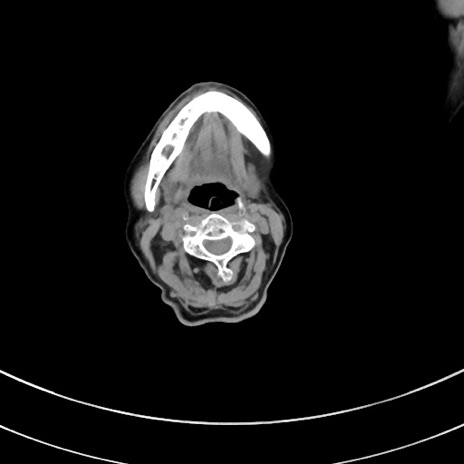

症例33(横断像)

【現病歴】延髄病変の精査・加療にて神経内科入院中。本日より心窩部痛あり。